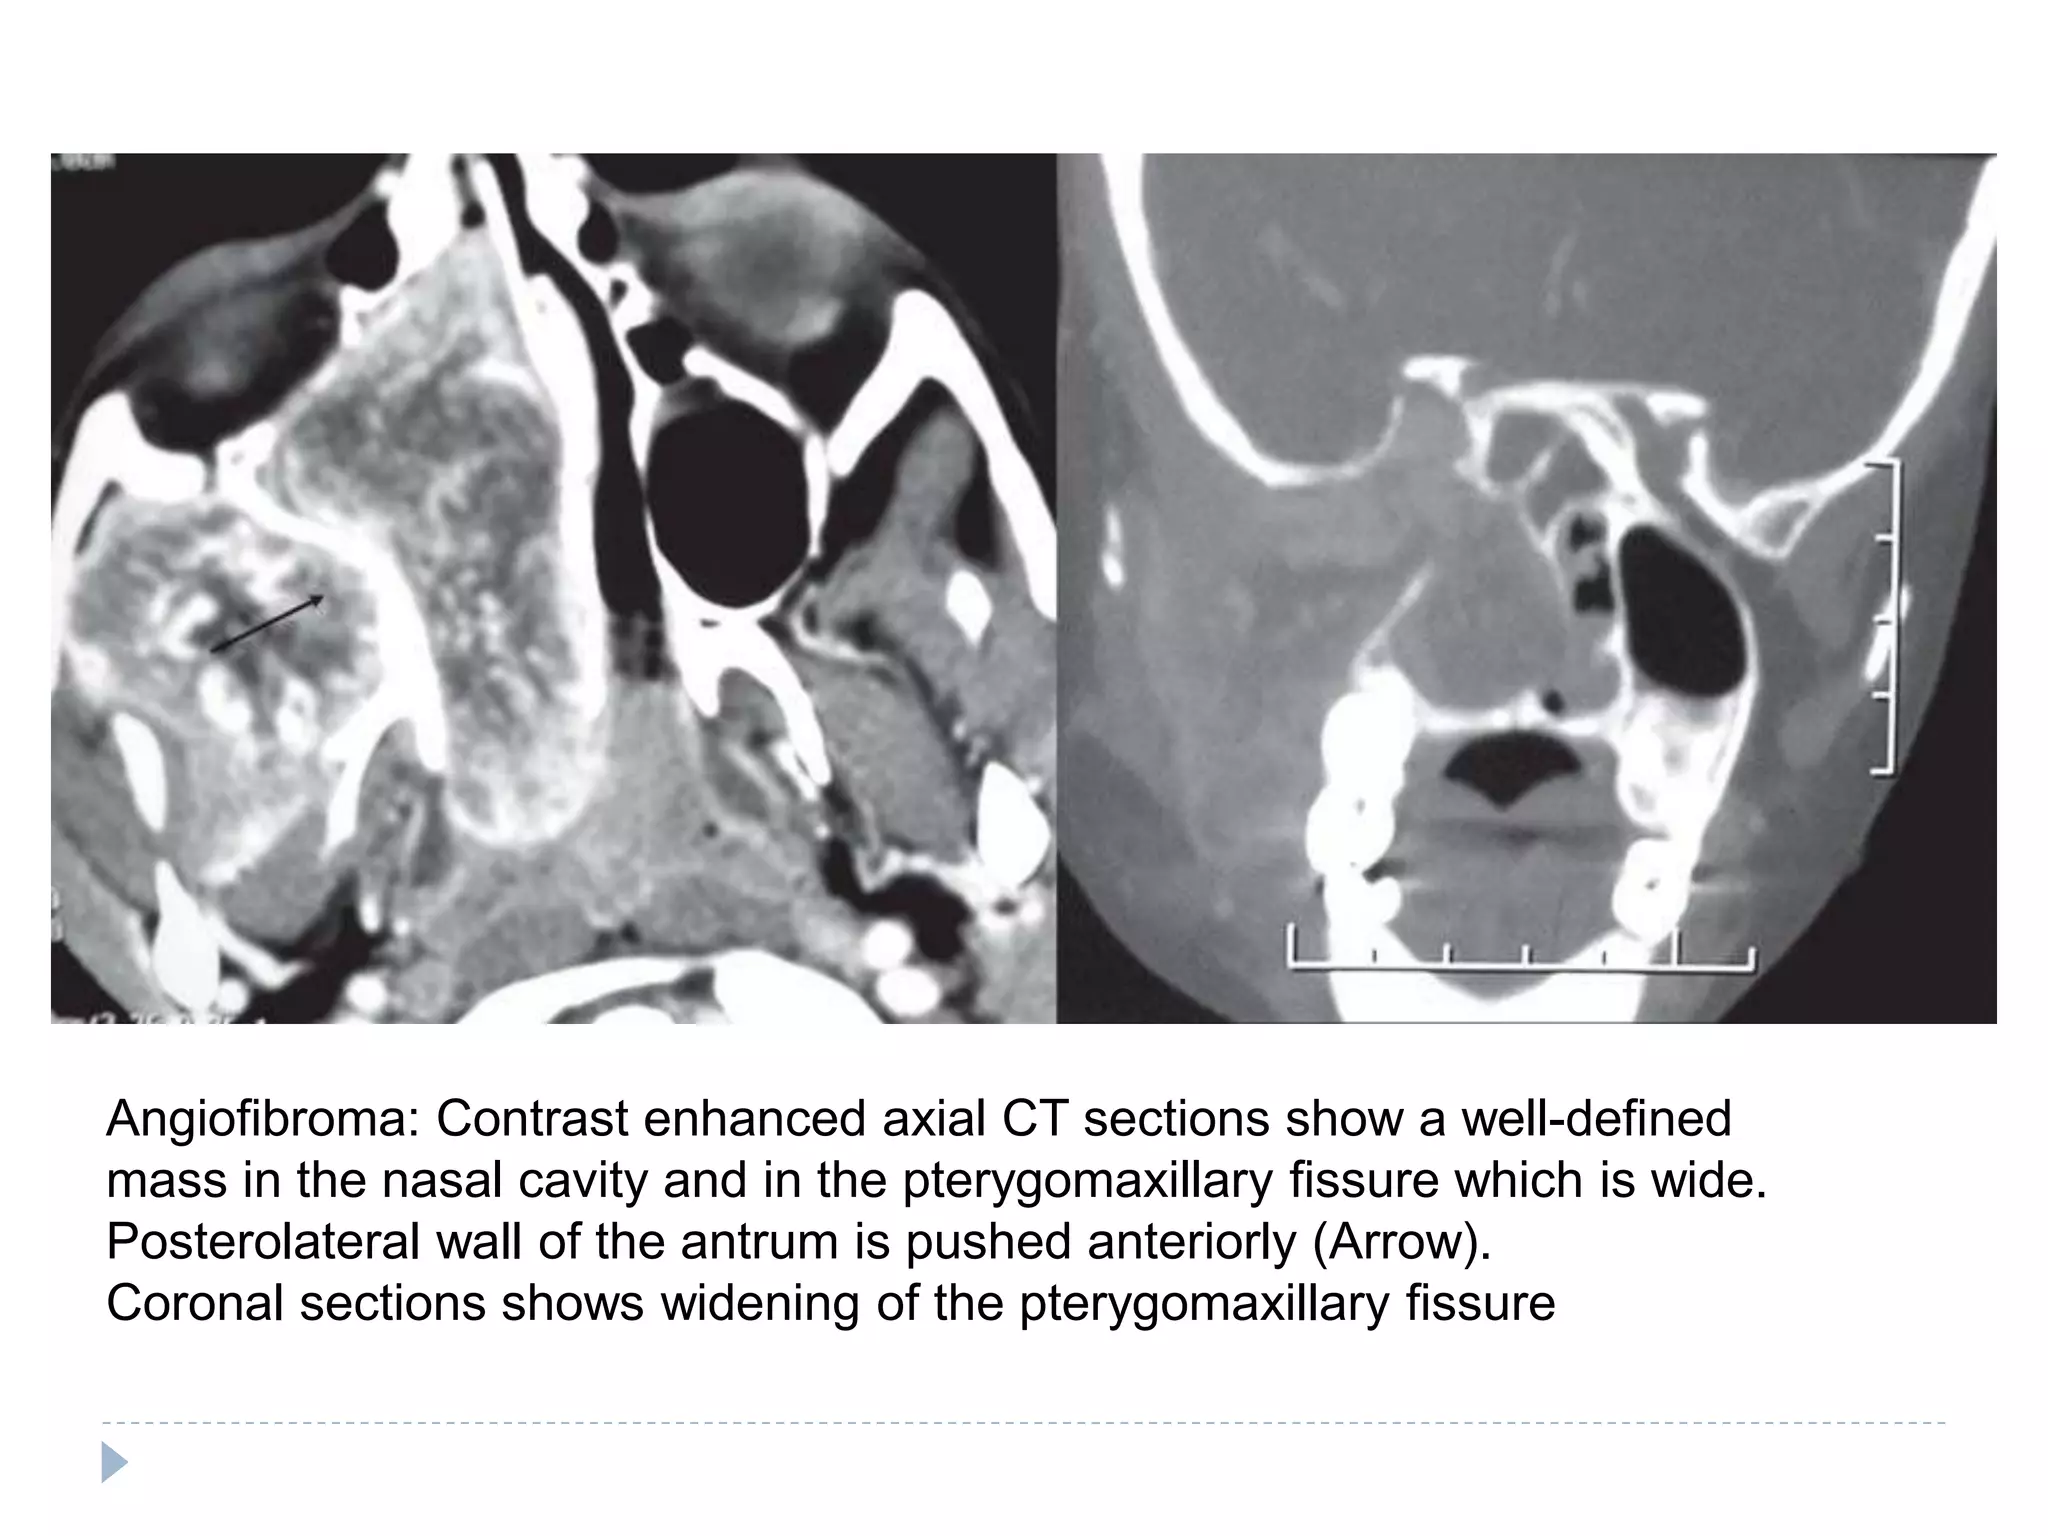

Angiofibroma: Contrast enhanced axial CT sections show a well-defined

mass in the nasal cavity and in the pterygomaxillary fissure which is wide.

Posterolateral wall of the antrum is pushed anteriorly (Arrow).

Coronal sections shows widening of the pterygomaxillary fissure